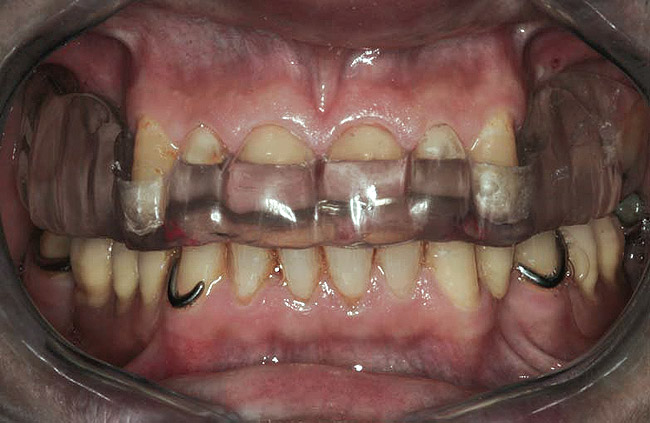

Figure 1  Intraoral anterior view of the patient presenting a severely worn maxillary dentition and loss of OVD.

Figure 1

Initial examination revealed a partial edentulous patient with extensive wear of the maxillary anterior teeth and moderate wear in the mandibular teeth (Figure 1, Figure 2, Figure 3 , Figure 4, Figure 5, Figure 6 and Figure 7). The patient's maxillary and mandibular RPDs also showed excessive wear and multiple signs of fractures (Figure 2 and Figure 3). The patient had been wearing a mandibular nightguard for 8 years.

A history of bruxing and consumption of acidic and carbonated drinks were reported. The clinical examination revealed severe tooth wear extending to the cervical level of the palatal surfaces of the maxillary teeth in some areas. Therefore, TSL was diagnosed as being caused by a combination of attrition and erosion.